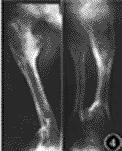

患者身上内生软骨瘤与内生软骨瘤病(亦即软骨发育者异常或ollier病)无任何区别。血管瘤则绝大多数为海绵状血管瘤,质软,多叶,无血管性搏动。亦有为毛细血管瘤淋巴管瘤以及血管错构瘤的报告往往伴有静脉曲张,静脉栓塞及静脉石形成。

常为双侧性,但单侧比较明显。常见于掌骨及指骨(87.8%)。病人智力发充正常,但身材较短小,约有12%的患者为侏儒,并且常有下肢不等长(36%)。有时可见拐状手,膝内翻、髋内翻、扁平足等继发性畸形。肢体的功能常因肿瘤而受损。骨骼病变常与血管瘤无直接关,即两者可以分别发生在不同的肢体。不产生疼痛。患者的内生软骨瘤的恶变率可达15.2~18.6%,而且在同一个病人身上可有数处发生恶变。血管瘤亦有恶变的报告。如果肿瘤范围扩大,以及在无外伤的情况下出现疼痛,均应及时活检。